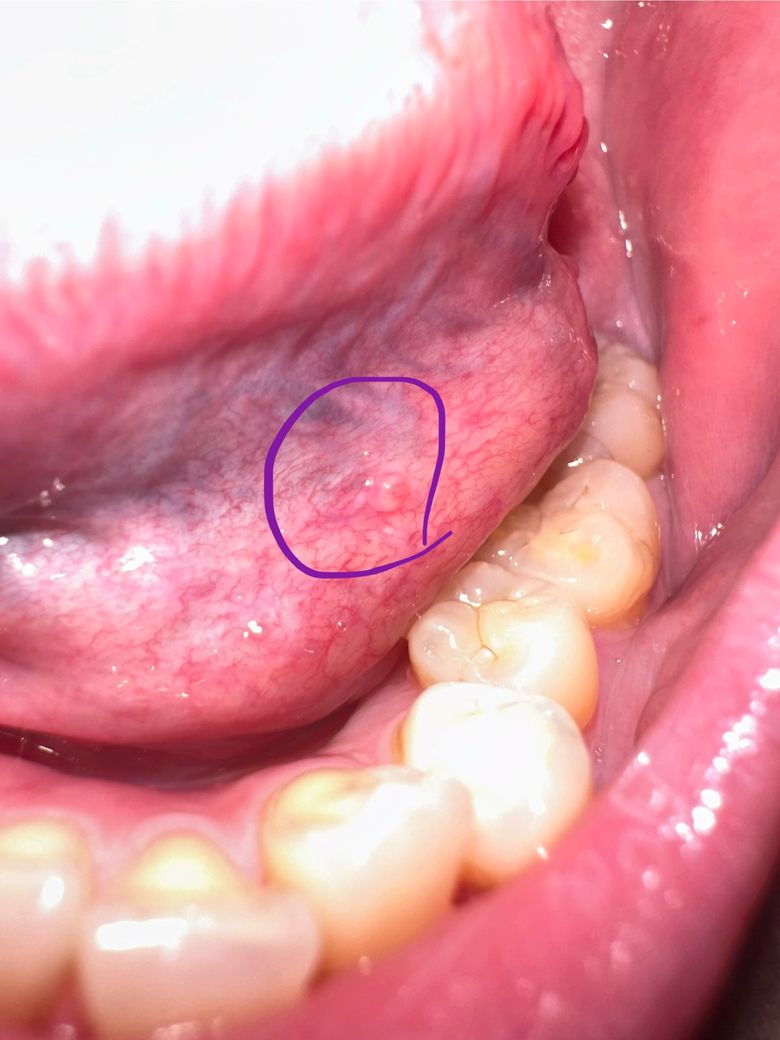

사진처럼 혀 왼쪽 아래 쪽에 볼록 뭔가 생겼어요!!

양쪽 동일하지는 않아요!!

통증도 없고 딱딱하지도 않아요!!

살짝 가끔뭐가 있다?는 느낌을 받아요

• 1번 째 사진